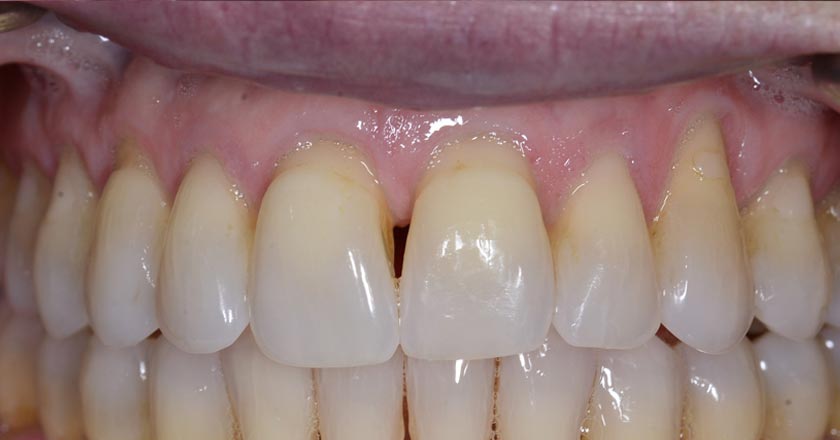

Gummy Smile - Before And After

Gummy smile correction – before treatment 2

Gummy smile correction – after treatment 2